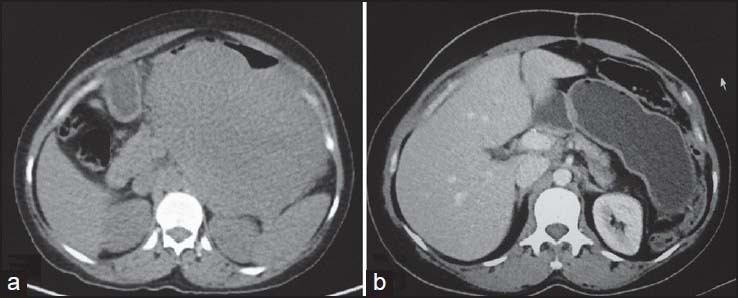

Complete surgical excision is the treatment of choice. Unlike carcinomas, resection of GISTs does not require wide bowel excision or lymphadenectomy as these tumors usually do not show lymph node metastases.[8] However, despite apparently complete resection with clear margins, the recurrence rate is high. Chemotherapy with imatinib mesylate, a tyrosine kinase inhibitor has been found to be highly effective in treatment of metastatic GIST. Imatinib mesylate has revolutionized the management of GIST. Now it is often used as the first-line treatment for unresectable, metastatic, or recurrent GIST. Although complete responses are rare, a large majority of patients with metastatic or inoperable GIST have either a partial response or disease stabilization after starting imatinib. Median survival rates have gone from <2>5 years since the advent of imatinib therapy.[11] Role of imaging also lies in response evaluation of patients treated with imatinib. Response to imatinib is characterized by decreased enhancement, resolution of the enhancing tumor nodules and a decrease in tumor neovascularity [Figures [Figures1616--20].20]. These changes are usually seen within 1-month of initiation of chemotherapy. Initially, tumors may enlarge during treatment due to intratumoral hemorrhage and myxoid degeneration. Enlargement with an overall decrease in tumor enhancement suggests a favorable response. Presence of new enhancing nodules within the tumor is consistent with recurrence.[12]

| Figure 20:Stomach gastrointestinal stromal tumors (GIST) postsurgery — (a) axial contrast-enhanced computed tomography showing heterogenously enhancing (arrow) stomach GIST (b) postsurgery, there is significant decrease in size with residual tumor showing minimal enhancement (arrow)

| Figure 20:Stomach gastrointestinal stromal tumors (GIST) postsurgery — (a) axial contrast-enhanced computed tomography showing heterogenously enhancing (arrow) stomach GIST (b) postsurgery, there is significant decrease in size with residual tumor showing minimal enhancement (arrow)